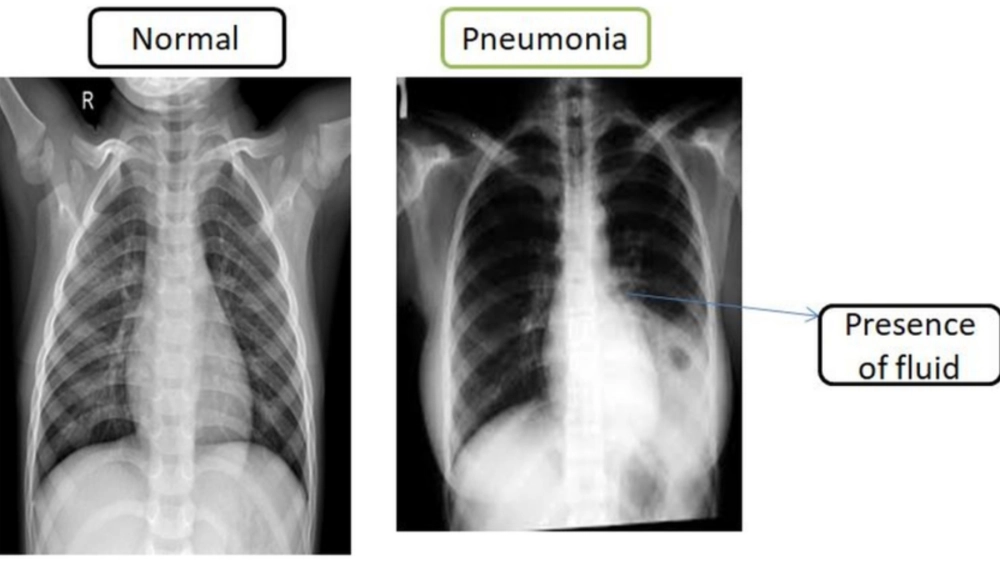

Hình ảnh chụp X-quang phổi của bệnh nhân bị viêm phổi

Tầm quan trọng của việc chụp X-quang phổi